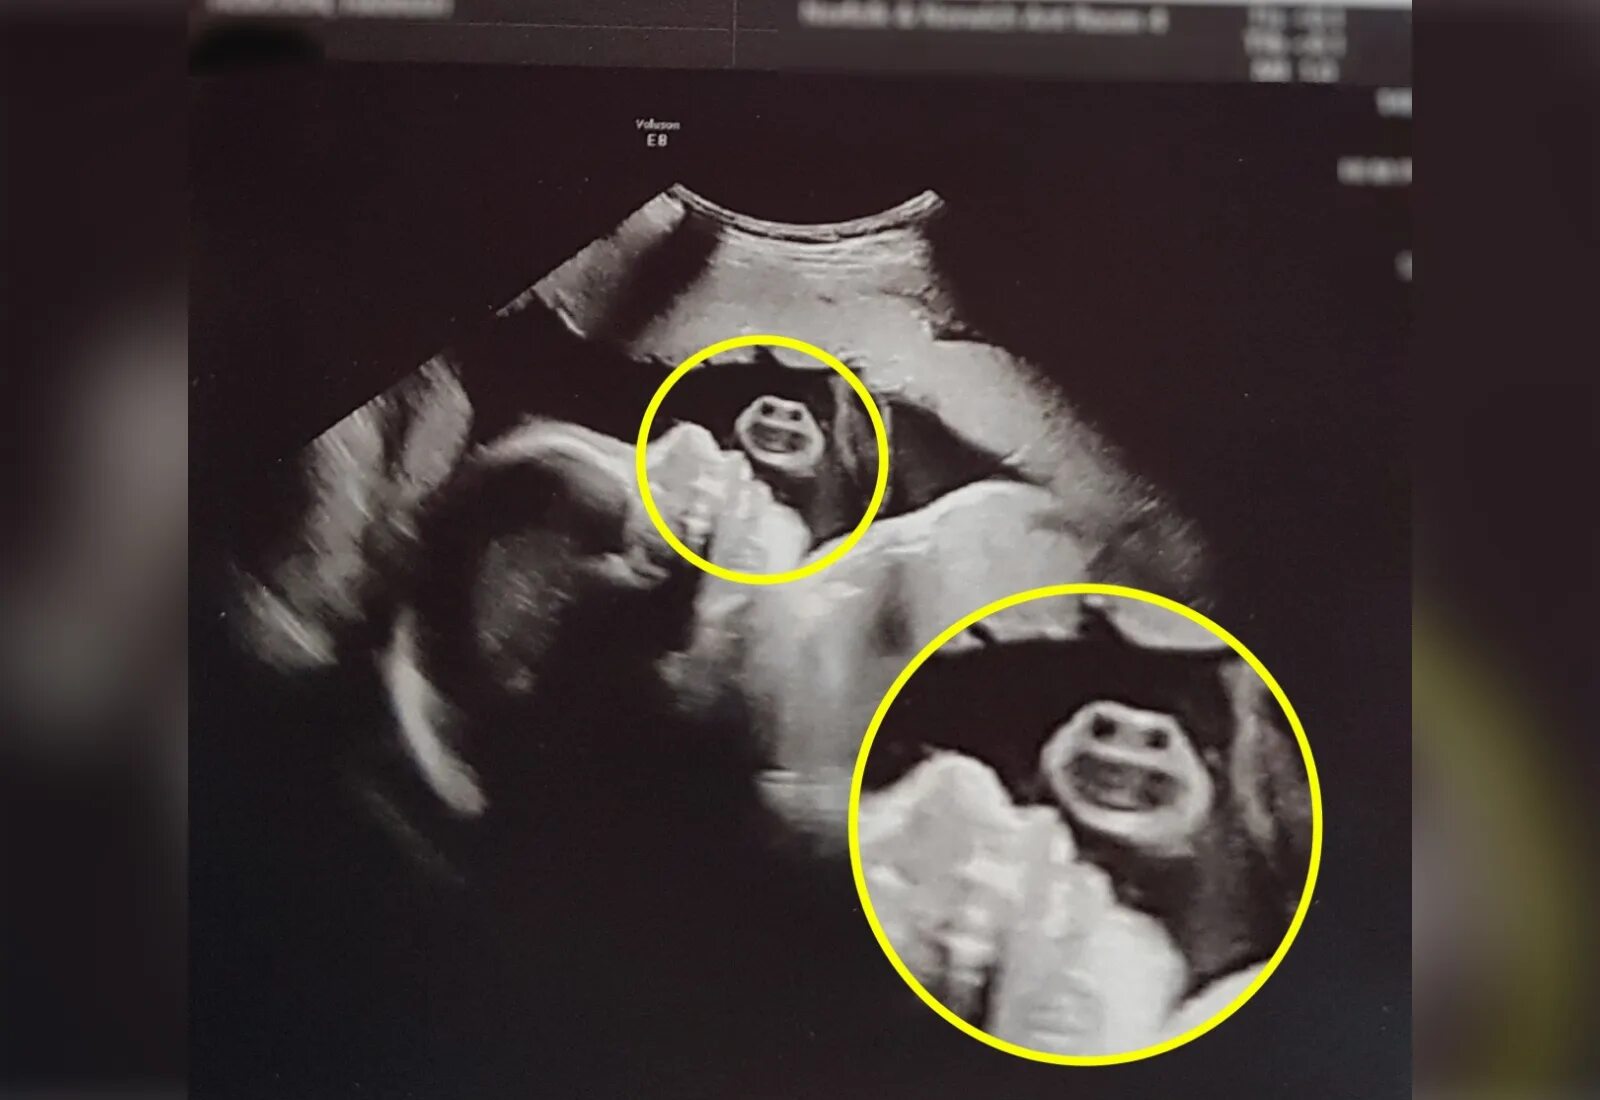

Дети видят беременностьДети видят беременностьДети видят беременностьСонник быть беременной. к чему снится беременность. к чему беременной снится. видеть себя беременной во сне.Дети видят беременностьДети видят беременностьДети видят беременностьДети видят беременностьДети видят беременностьК чему снится беременность. к чему беременной снится. сонник быть беременной.Дети видят беременностьРыба снится к беременности. алекса беременна. сны предсказывающие беременность. ребенок предсказывает беременность.Видеть во сне себя беременной с животом к чему. видеть во сне беременную себя с большим животом. во сне видеть себя беременной с животом для женщин незамужней к чему. к чему снится беременность своя девушке незамужней.Дети видят беременностьК чему снится беременность. к чему снитс ябеременость. к чему беременной снится. беременность во сне к чему снится.Дети видят беременностьК чему снится беременность. беременность сонник для женщины. чюк чему снится беременность.Беременность. беременность и рождение ребенка.Дети видят беременностьДети видят беременностьДети видят беременностьДети видят беременностьДети видят беременностьБеременные дети. дети и беременные фотосток.Дети видят беременностьБеременной снится двойня. к чему беременной снится двойня. к чему снится забеременеть двойней. к чему снится беременность двойняшками.Дети видят беременностьДети видят беременностьДети видят беременностьДети видят беременностьДети видят беременностьДети видят беременностьДети видят беременностьСонник беременность во сне. снится родить ребенка во сне незамужней. сон родила ребенка к чему это. сонник к чему снится рождения ребёнка.Девушка забеременела. ложная беременность у женщин фото. лекции для беременных.К чему снится беременность. беременность во сне к чему.Дети видят беременностьК чему снится беременность своя. рожать во сне к чему снится беременной женщине. к чему снятся роды во сне женщине не беременной. сонник беременной приснилось что родила подруга.Беременность. беременные. картинки беременных.Беременность wikihow. беременность спать. рисунки рабочей беременной женщины.Дети видят беременностьДети видят беременностьДети видят беременностьДети видят беременностьДети видят беременностьДети видят беременностьДети видят беременностьДети видят беременностьДети видят беременностьВидеть во сне беременную женщину. желательная беременность. прогулки и сон беременных.Дети видят беременностьДети видят беременностьДети видят беременностьК чему снится беременность. к чему снится беременнос. беременность во сне к чему.Беременность для презентации. ранняя беременность. зож и беременность. последствия ранней беременности презентация.Дети видят беременностьДети видят беременностьДети видят беременностьДети видят беременностьДети видят беременностьДети видят беременностьКороткая стрижка и беременность. красота беременности. беременность и волосы. беременные со стрижкой.Сон беременной женщины. беременность во сне. видеть во сне беременную женщину. к чему снится что беременна во сне.Беременный живот. беременность животик. фото беременных животиков. фото беременных на ранних сроках.Дети видят беременностьДети видят беременностьДети видят беременностьПоздравление с беременностью сестре. чюк чему снится беременность.Дети видят беременностьДети видят беременностьДети видят беременностьБеременность фон.Дети видят беременностьДети видят беременностьДети видят беременностьДети видят беременностьК чему снится беременность. к чему снитс ябеременость. к чему беременной снится. сонник беременность во сне.Дети видят беременность